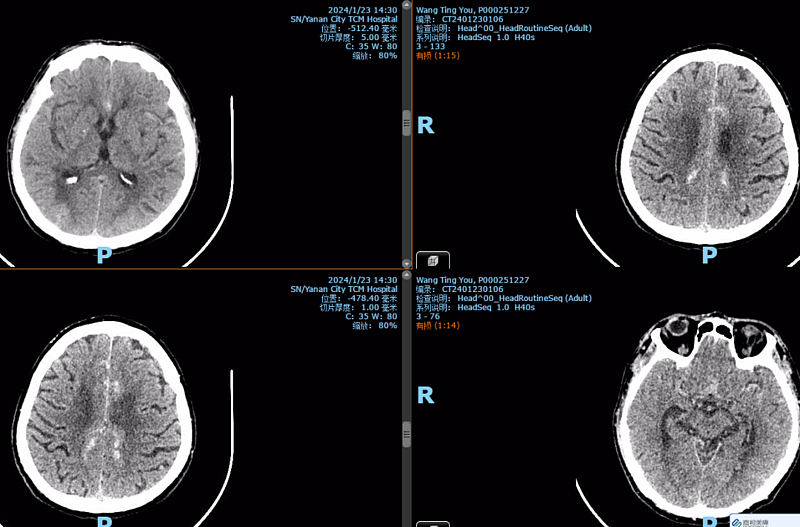

入院后患者查颅脑CT见蛛网膜下腔出血,北京驻延脑外科专家陈素华,脑外科主任田德洲和董永军副主任详细查看患者病情、结合患者2次脑梗死病史及相关检查结果,考虑患者大脑前动脉瘤破裂出血可能,需要手术治疗。脑外科团队立即向患者家属详细告知患者病情,并征得患者家属同意。

头颈CTA可见右侧大脑前动脉A3段动脉瘤破裂,主动脉弓憩室。